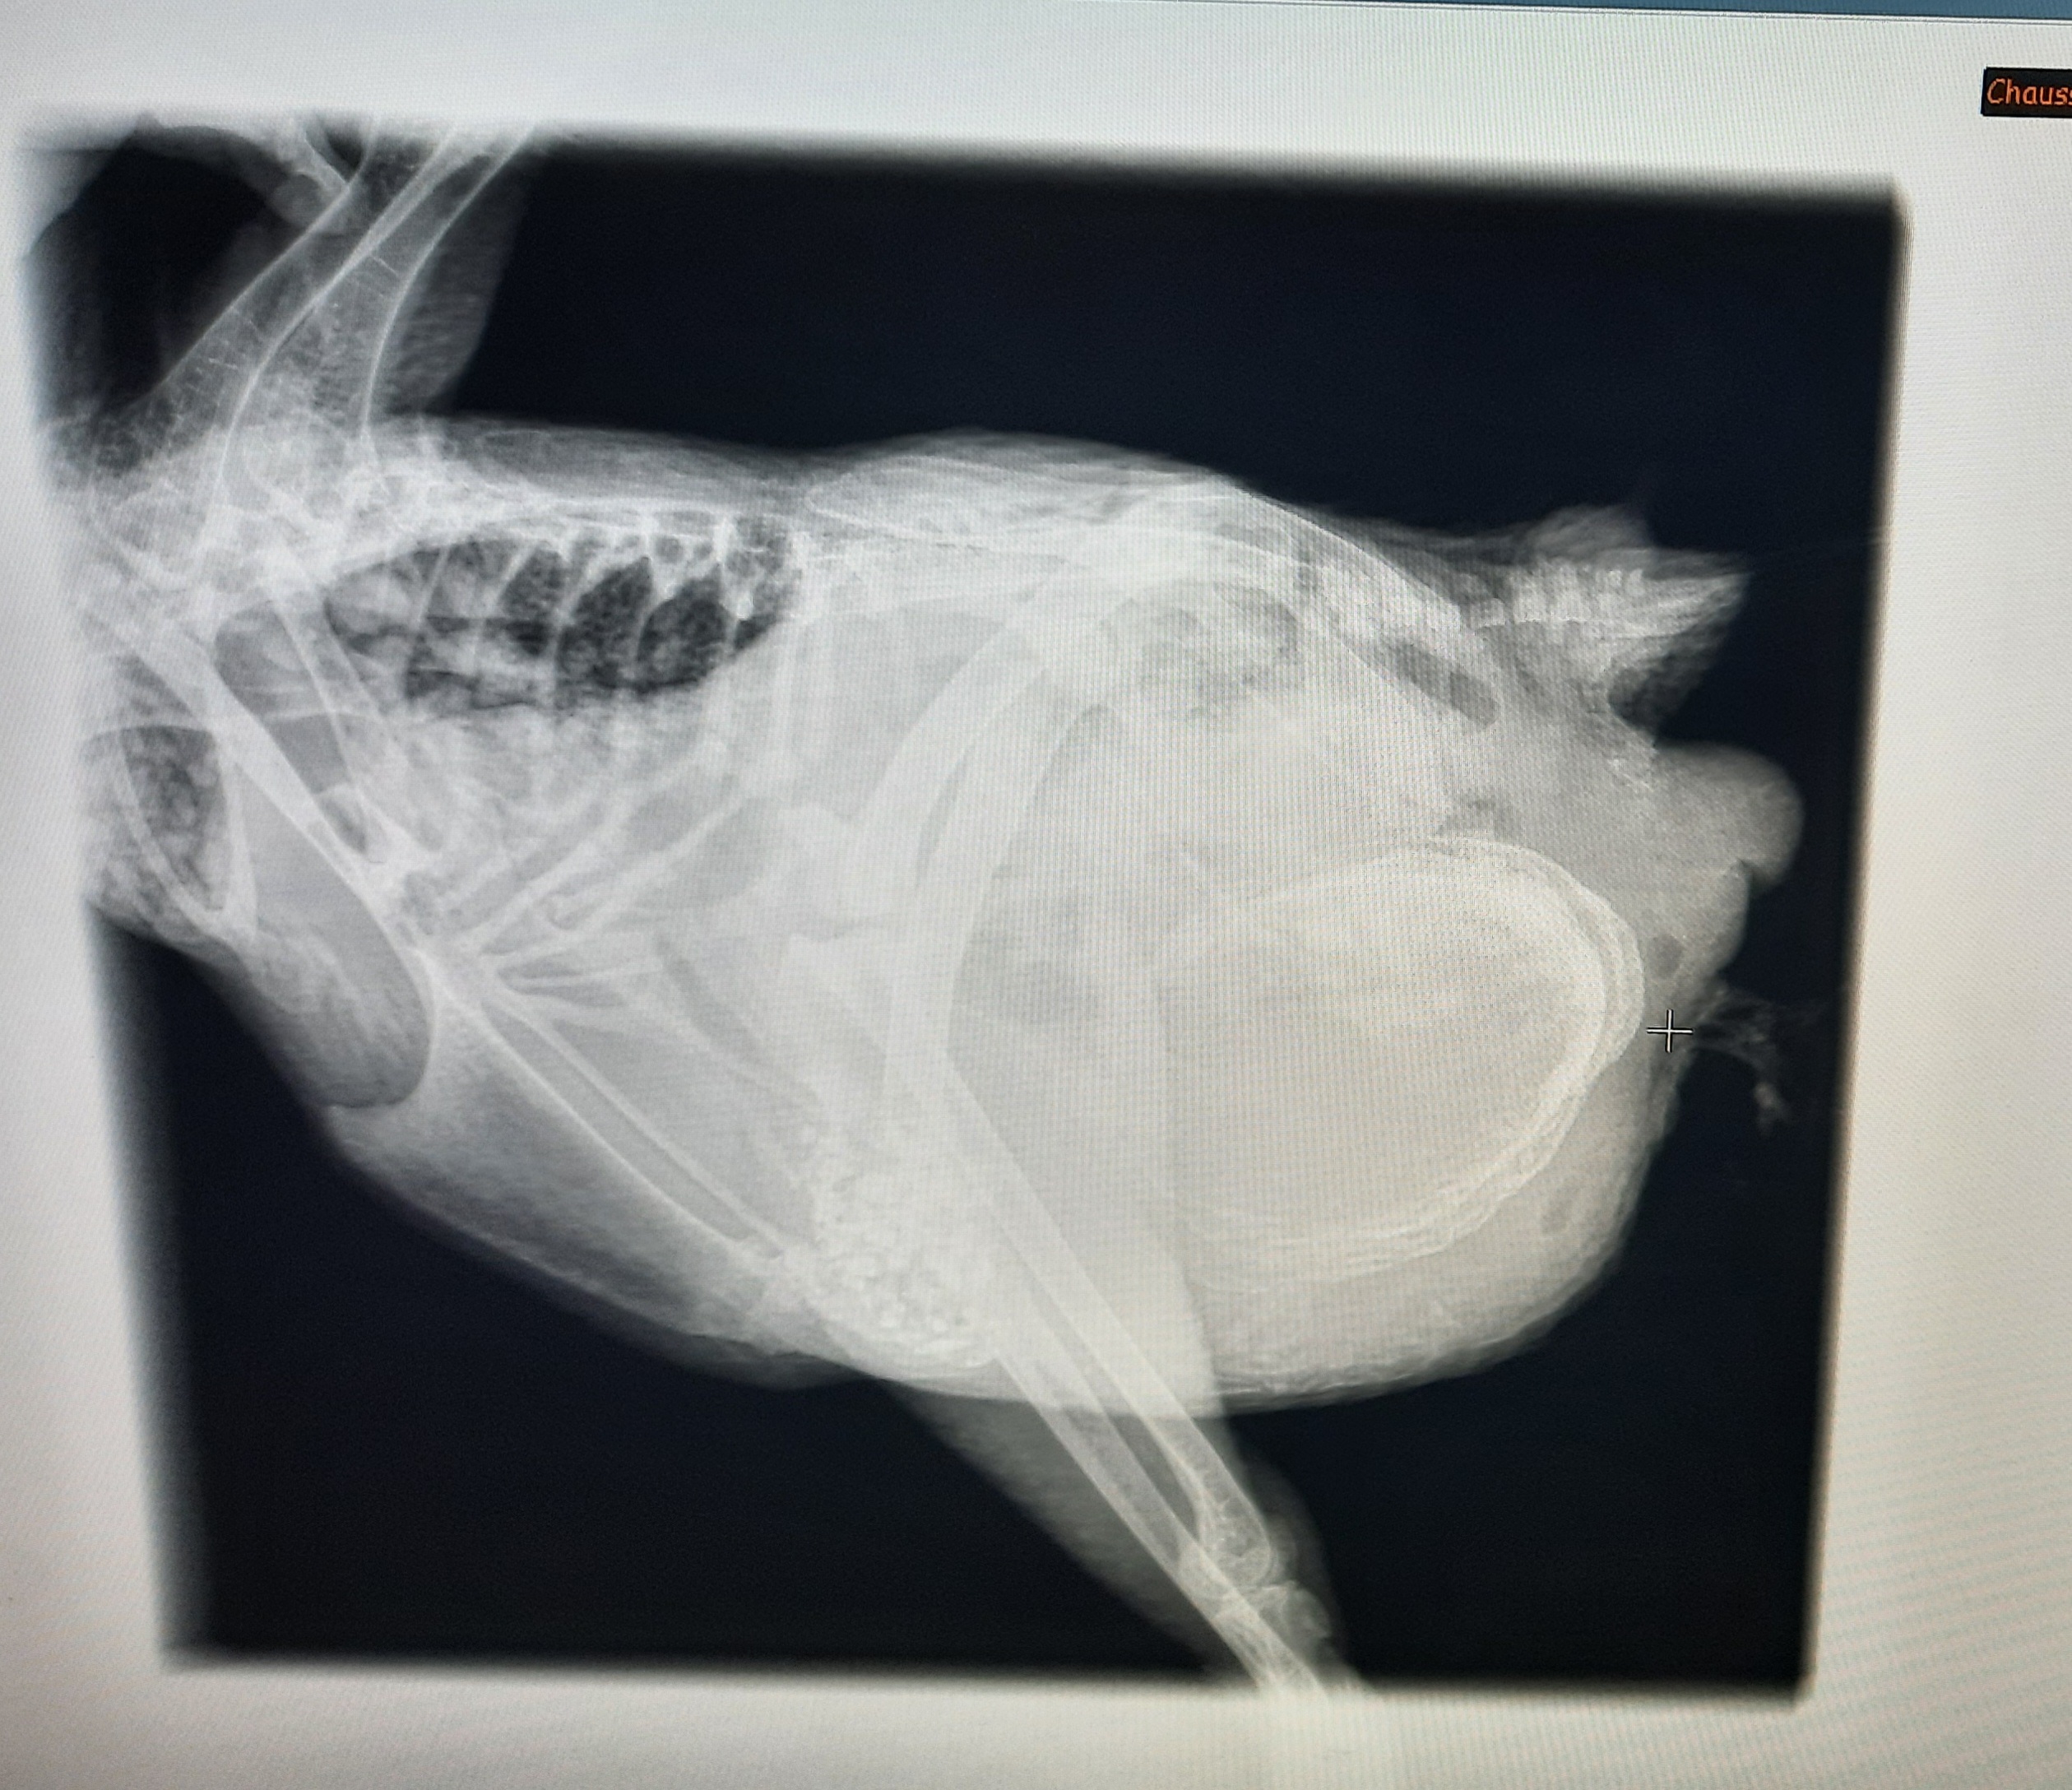

L'une de nos poules récemment sortie d'élevage présentait des problèmes de ponte et a été opérée après la détection d'une masse à la radio...

Voici ce qui a été extrait de son abdomen.

des fibrines, et une accumulation de jaunes d'oeufs dans l'oviducte, qui a été enlevé pour la sauver: la poule ne parvenait plus à faire un oeuf normal et ils s'accumulaient dans l'oviducte sans jamais sortir. Il était donc grand temps de l'aider!